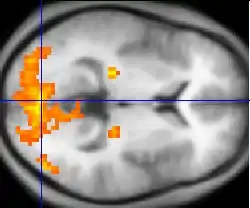

Functional neuroimaging is the use of neuroimaging technology to measure an aspect of brain function, often with a view to understanding the relationship between activity in certain brain areas and specific mental functions. It is primarily used as a research tool in cognitive neuroscience, cognitive psychology, neuropsychology, and social neuroscience.

PET, fMRI, fNIRS and fUS can measure localized changes in cerebral blood flow related to neural activity. These changes are referred to as activations. Regions of the brain which are activated when a subject performs a particular task may play a role in the neural computations which contribute to the behaviour. For instance, widespread activation of the occipital lobe is typically seen in tasks which involve visual stimulation (compared with tasks that do not). This part of the brain receives signals from the retina and is believed to play a role in visual perception.

Traditional "activation studies" focus on determining distributed patterns of brain activity associated with specific tasks. However, scientists are able to more thoroughly understand brain function by studying the interaction of distinct brain regions, as a great deal of neural processing is performed by an integrated network of several regions of the brain. An active area of neuroimaging research involves examining the functional connectivity of spatially remote brain regions. Functional connectivity analyses allow the characterization of interregional neural interactions during particular cognitive or motor tasks or merely from spontaneous activity during rest. FMRI and PET enable creation of functional connectivity maps of distinct spatial distributions of temporally correlated brain regions called functional networks. Several studies using neuroimaging techniques have also established that posterior visual areas in blind individuals may be active during the performance of nonvisual tasks such as Braille reading, memory retrieval, and auditory localization as well as other auditory functions.[3]

Functional neuroimaging studies have to be carefully designed and interpreted with care. Statistical analysis (often using a technique called statistical parametric mapping) is often needed so that the different sources of activation within the brain can be distinguished from one another. This can be particularly challenging when considering processes which are difficult to conceptualise or have no easily definable task associated with them (for example belief and consciousness).